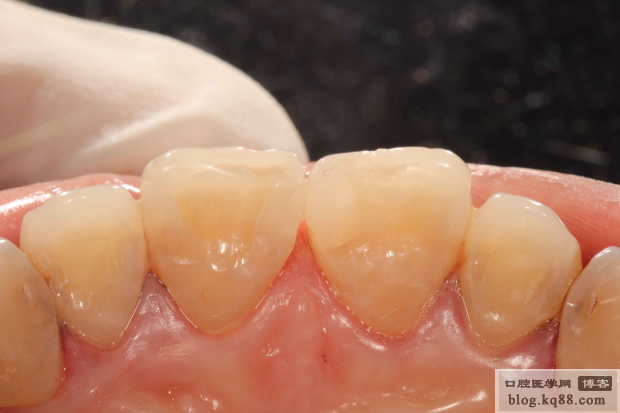

隔日修整初步拋光